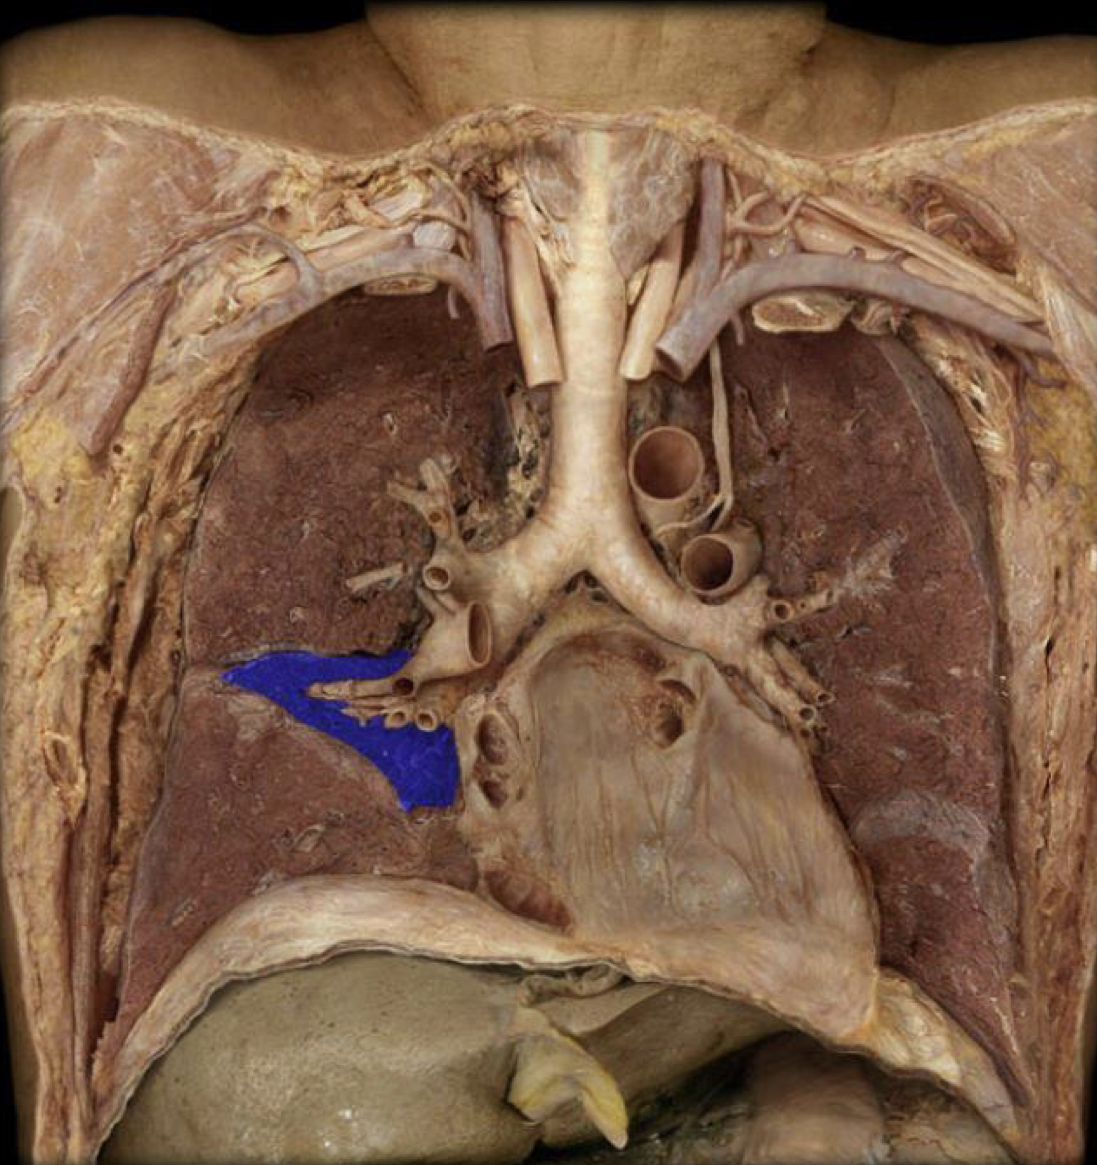

What structure is highlighted in blue?

Trachea (lower respiratory)